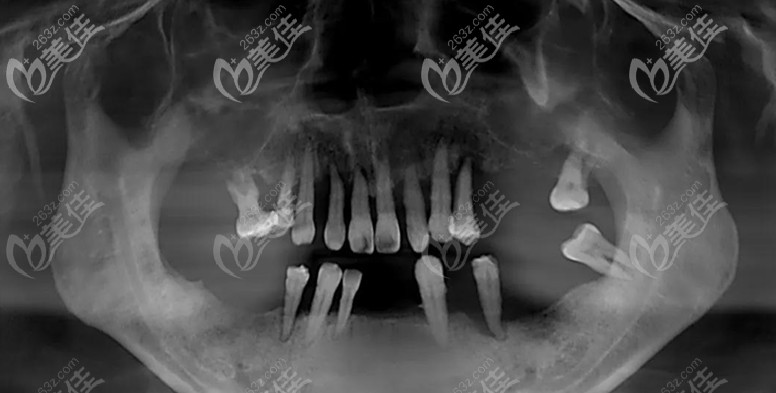

▲種植前的口腔照

了解到顧客對功能和美觀的需求,鑒于顧客上頜牙槽骨骨質(zhì)疏松+萎縮的特殊情況,為其制定了上頜穿翼板VIIV即刻種植+下頜即刻種植即刻修復(fù)方案。